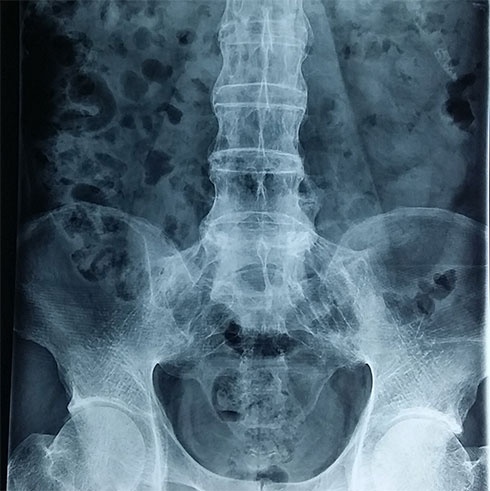

| Hình ảnh chụp khớp cùng chậu của một bệnh nhân. |

Khi chụp X-quang khớp cùng chậu sẽ thấy các thương tổn khớp này như thoái hóa khớp, dính khớp hay hủy mặt khớp. Chụp MRI và chụp khảo sát đồng vị phóng xạ cho biết tình trạng viêm nhiễm, hủy xương hay các dấu hiệu khác.